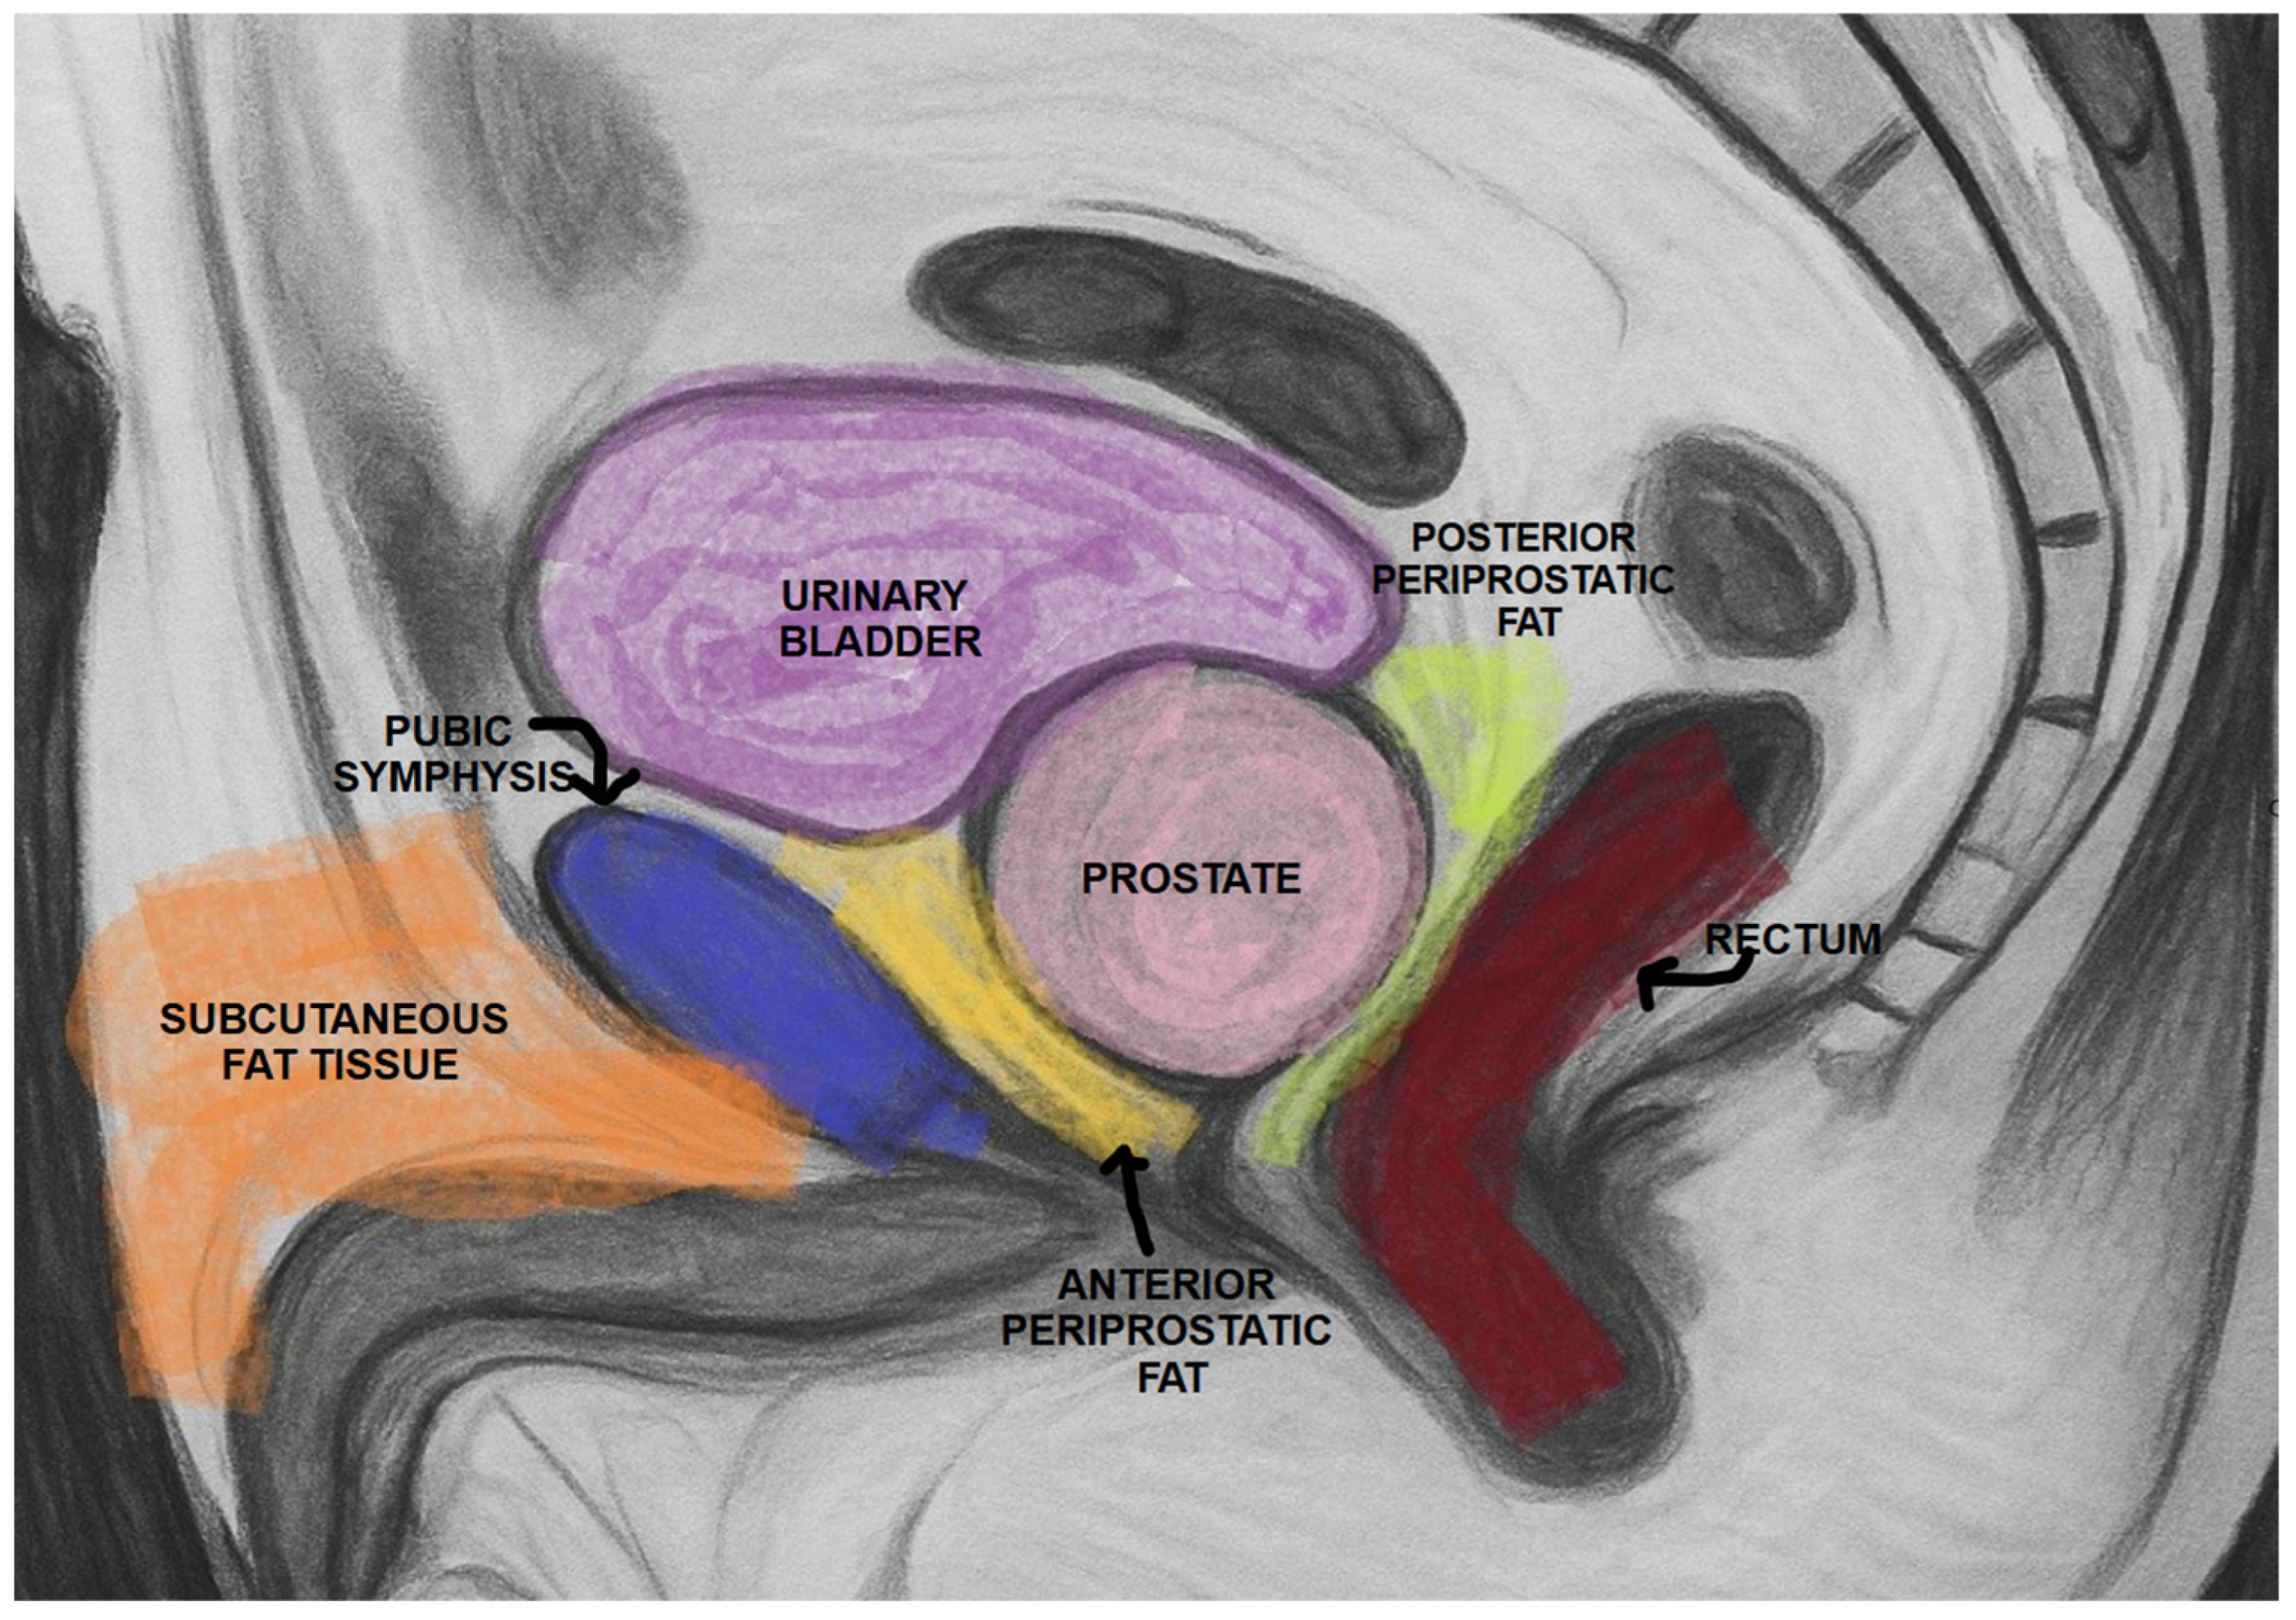

PPATT was measured as the shortest vertical distance from the pubic symphysis to the anterior surface of the prostate on midsagittal images; SATT was measured on the same slice as PPATT, defined as the shortest vertical distance from the pubic symphysis to the overlying skin, while PPPATT was measured as the shortest distance from the posterior surface of the prostate and anterior wall of the rectum. The images below represent the visual explanation of these measurements (Figure 2 and Figure 3).

Figure 3. Measurement of PPAT (red line), posterior PPAT (yellow line), and SATT (green line) on a midsagittal view, T2 sequence, on a prostate MRI categorized as PI-RADS 4, showing a heterogeneous prostate gland that indents and protrudes into the urinary bladder.